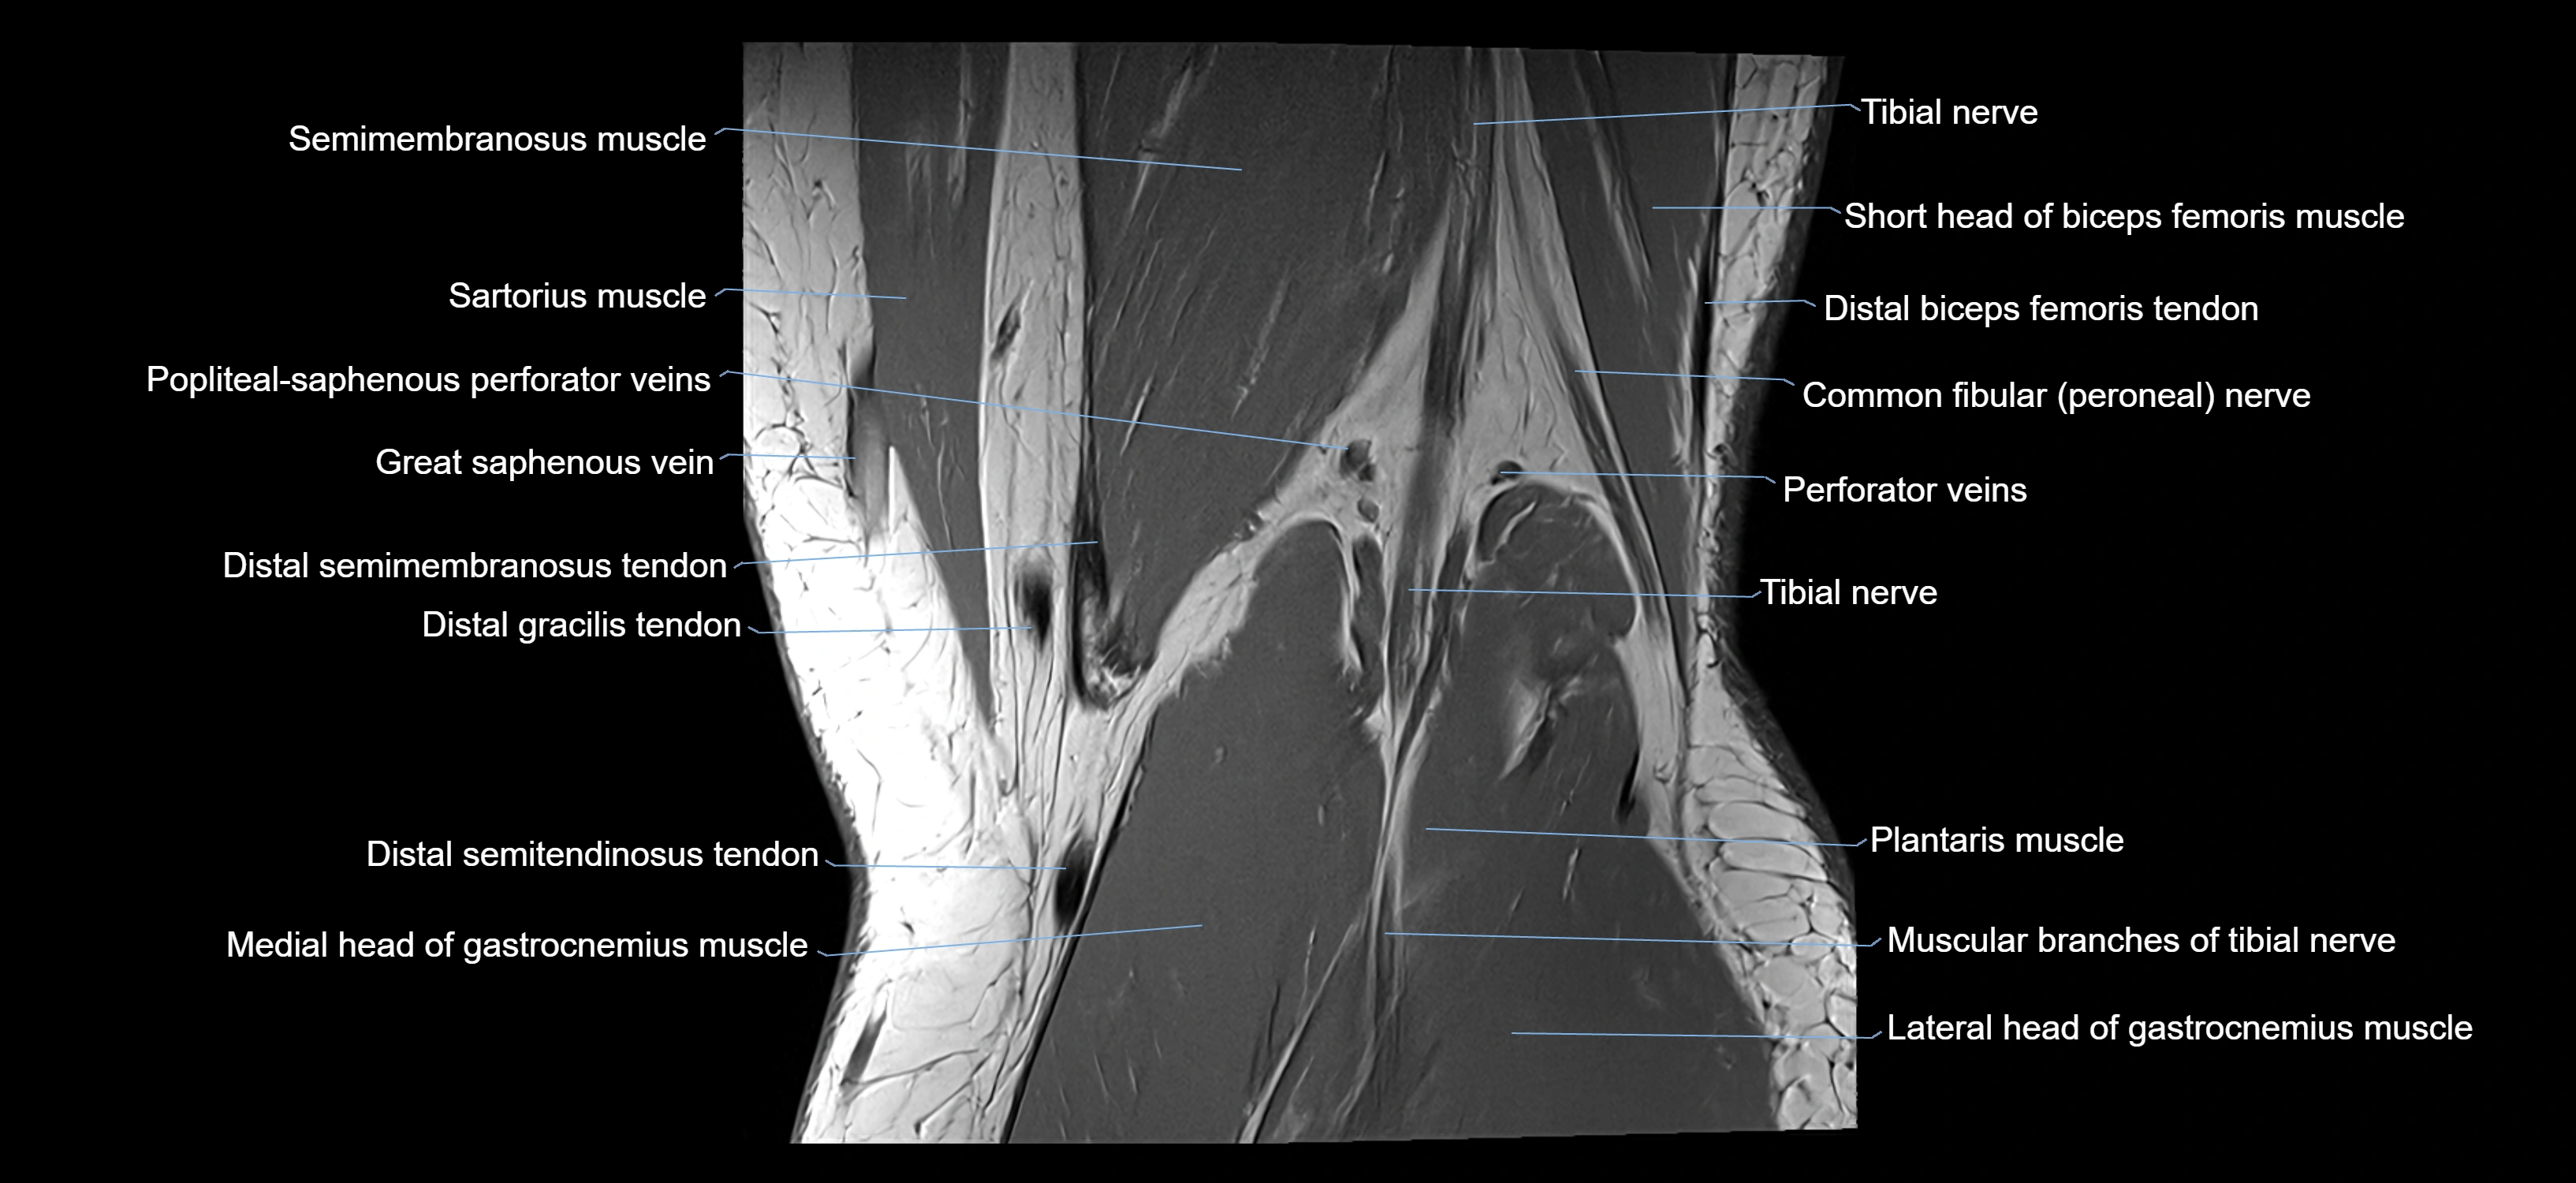

- Common fibular nerve

- Distal biceps femoris tendon

- Distal semimembranosus tendon

- Distal semitendinosus tendon

- Gracilis tendon (Distal)

- Lateral head of gastrocnemius muscle

- Medial head of gastrocnemius muscle

- Muscular branches of tibial nerve

- Plantaris muscle

- Popliteal artery

- Popliteal vein

- Popliteal–Saphenous perforating veins

- Sartorius muscle

- Semimembranosus muscle

- Tibial nerve